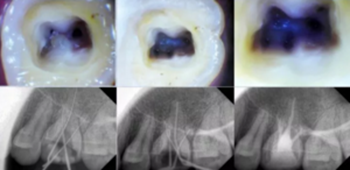

開髓去腐質(zhì)

根管治療開髓前必須去凈腐質(zhì),然后換用另一根新的車針(裂鉆或金剛砂車針均可,但金剛砂車針開髓震動感少,開髓穩(wěn))進(jìn)入髓腔,穿通髓腔后換高速球鉆揭頂,揭頂一定要全,以能看清整個髓室底為準(zhǔn),然后換用裂鉆或金剛砂車針修整髓壁。

這一步質(zhì)控的標(biāo)準(zhǔn)是:

①去凈腐質(zhì)和原有充填物。

②揭凈髓頂,看到整個髓底解剖結(jié)構(gòu)。

③髓壁與根管壁連續(xù)流暢。

④沒有牙頸部臺階,沒有過度切割髓壁和髓底。